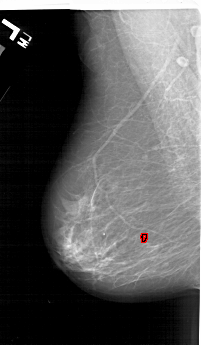

A_1124_1.LEFT_CC

LEFT_CC LINES 6331 PIXELS_PER_LINE 3376 BITS_PER_PIXEL 12 RESOLUTION 43.5 OVERLAY

FILE: A_1124_1.LEFT_MLO.OVERLAY

TOTAL_ABNORMALITIES 1

ABNORMALITY 1

LESION_TYPE CALCIFICATION TYPE PLEOMORPHIC DISTRIBUTION LINEAR

ASSESSMENT 4

SUBTLETY 1

PATHOLOGY MALIGNANT

TOTAL_OUTLINES 1